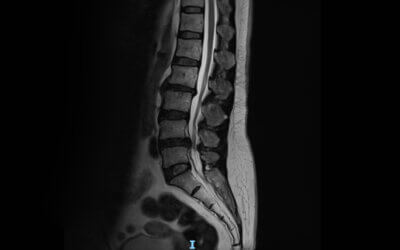

• Spinal Decompression

Spinal Decompression for Degenerative Disc Disease | Swolensky Method Henderson NV

What Happens Inside a Spinal Disc During Decompression?